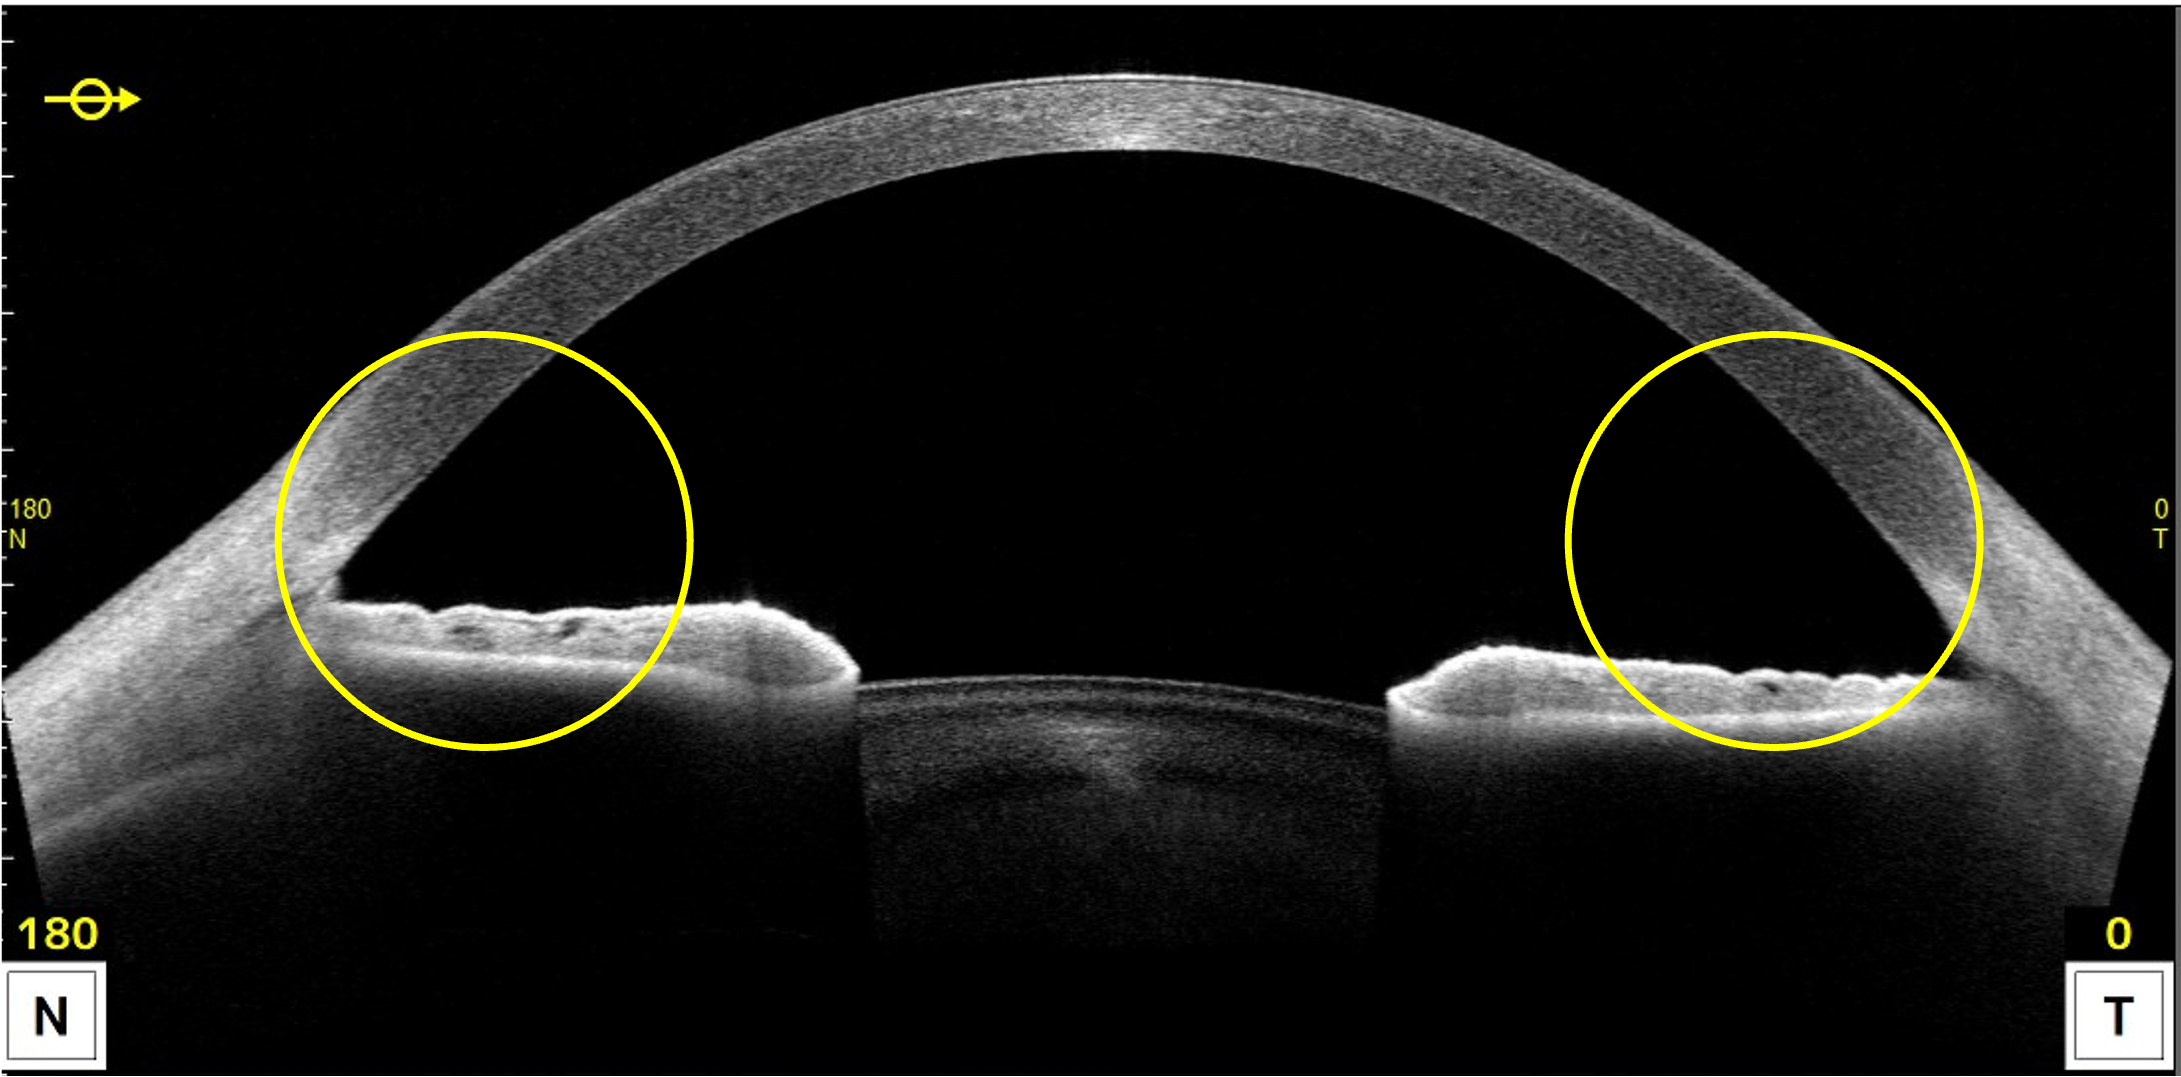

そのため、「前眼部OCT」という検査機器で、眼の断面を詳しく測定し、ぴったりのサイズを選んでいきます。

まず確認するのは、眼の中のスペースです。

ICLは虹彩(茶目の部分)と水晶体の間に入れるので、その空間が十分かどうかを「前房深度」という指標でチェックします。

次に、白目と黒目の境目の幅(WTW)や眼の奥行きを測り、適切なサイズを導き出します。